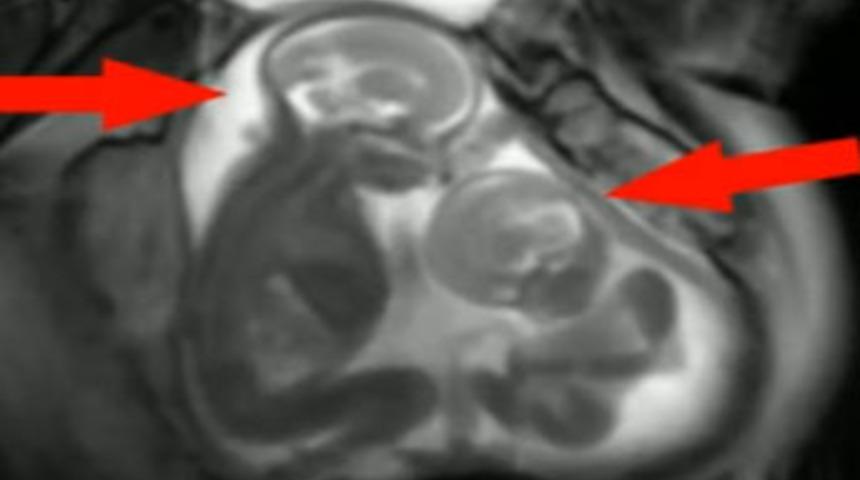

Londra Üniversitesi'nde ikizlerin anne karnında gelişimi ile ilgili yapılan bir araştırmada ilginç bir görüntü yakalandı.

İkizlerden biri anne karnında kardeşini tekmeliyordu. Bebeklerden biri diğerini tekmelerken, tekmelenen bebeğin ikizini nasıl köşeye sıkıştırdığı da dikkatlerden kaçmadı.